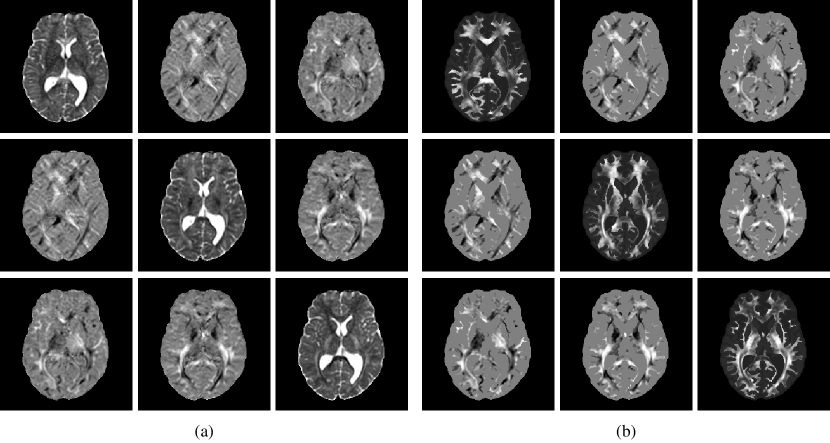

For reasons that will become clearer in Section 2.4, a unit tumour cell diffusion tensor was built at this stage by fixing dwhitesubscript𝑑whited_{\rm white} to 1.0. A value of 0.1 was chosen for the dgrey/dwhitesubscript𝑑greysubscript𝑑whited_{\rm grey}/d_{\rm white} ratio, as proposed previously in [11] to account for the restricted migration of tumour cells in grey compared to white matter. This ratio was supposed constant among all subjects as it is expected to depend exclusively on the structural organisation of healthy white versus grey matter and not on the tumour characteristics. Similarly, the anisotropy factor a𝑎a was fixed to 10 for all subjects, as suggested in [12]. An example of processed DTI data is depicted in Figure 2. The processed MR data of the 6 volunteers used in this study are publicly available at https://lisaserver.ulb.ac.be/owncloud/index.php/s/KwEPG65gh1U7xNM. Further details on these data are available in Appendix B.

Refer to caption

Figure 2: Example of processed DTI data. (a) DTI-derived water diffusion tensor field after susceptibility-induced distortion, eddy currents, and patient motion correction using FSL. (b) Tumour diffusion tensor field with increased anisotropy in white matter (a=10𝑎10a=10) and scaled diffusivity (dgrey/dwhite=0.1subscript𝑑greysubscript𝑑white0.1d_{\rm grey}/d_{\rm white}=0.1) built from the water diffusion tensor field in panel (a) and the brain map in Figure 1(c) as described in Section 2.3.6. The subpanel located at row i𝑖i and column j𝑗j of panels (a) and (b) corresponds to the tensor component di,jsubscript𝑑𝑖𝑗d_{i,j}.